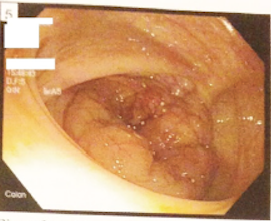

A 75-year-old man developed sharp left upper quadrant pain immediately following an esophagogastroduodenoscopy (EGD) and colonoscopy performed for persistent generalized abdominal discomfort.